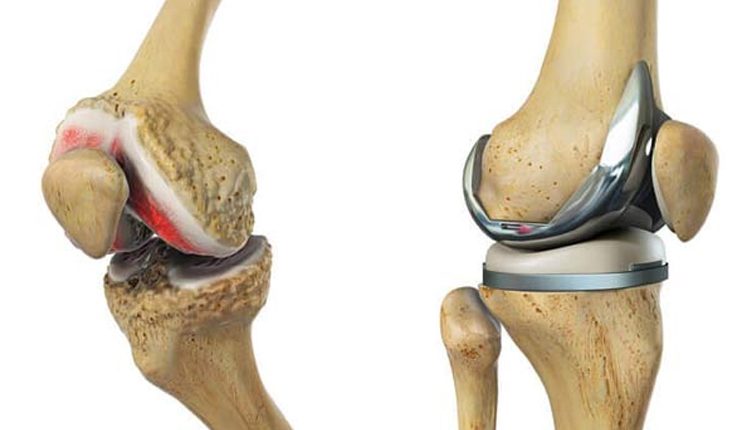

+التهاب مفصل

عوامل متعددی میتواند موجب التهاب مفاصل شود که آرتروز، روماتیسم و آرتریت از مصادیق مختلف آن هستند. با ایجاد التهاب، مفاصل زانو کارکرد خود را در بدن از دست داده و موجب بروز علائمی همچون درد، تورم و محدودیت حرکتی در افراد میشوند.

- انواع آرتریت زانو